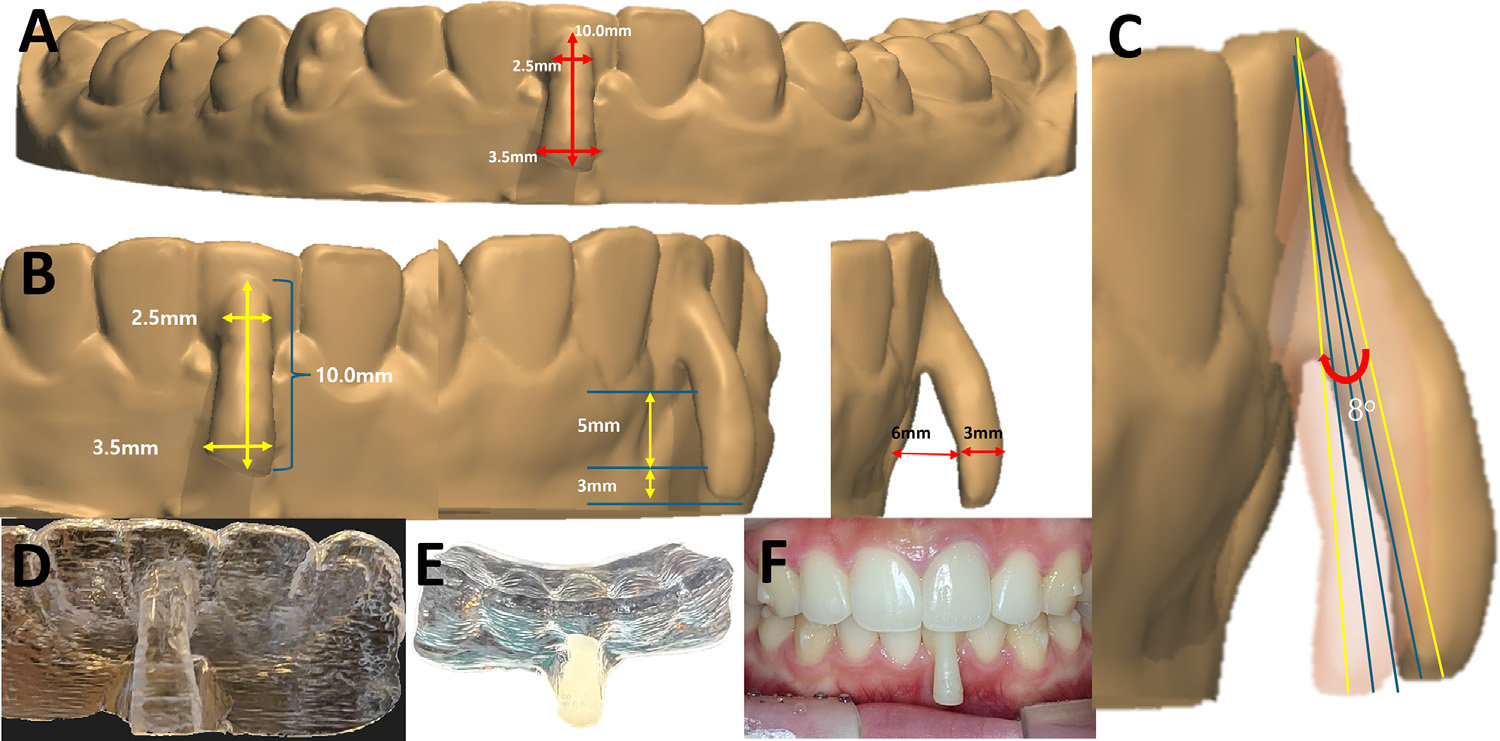

‘오버행잉 어태치먼트’는 치근 이동 시 발생하는 토크(torque)를 정밀 제어해, 치아의 중심저항점(center of resistance)에 가까운 위치에서 힘을 전달하도록 설계됐다. 이를 통해 정확한 치체이동(root movement)이 가능해지고, 결과적으로 잇몸재생이 유도된다.

이번 논문은 국내 최초로 투명교정만으로 퇴축된 잇몸을 재생시킨 임상 보고로, 하악 전치부에서 5mm의 잇몸퇴축이 11개월간의 교정치료 후 1mm로 회복되는 임상 결과를 확인했다. 치조골과 잇몸조직이 자연스럽게 복원되는 과정을 객관적 데이터로 제시했다는 점에서 의미가 크다.